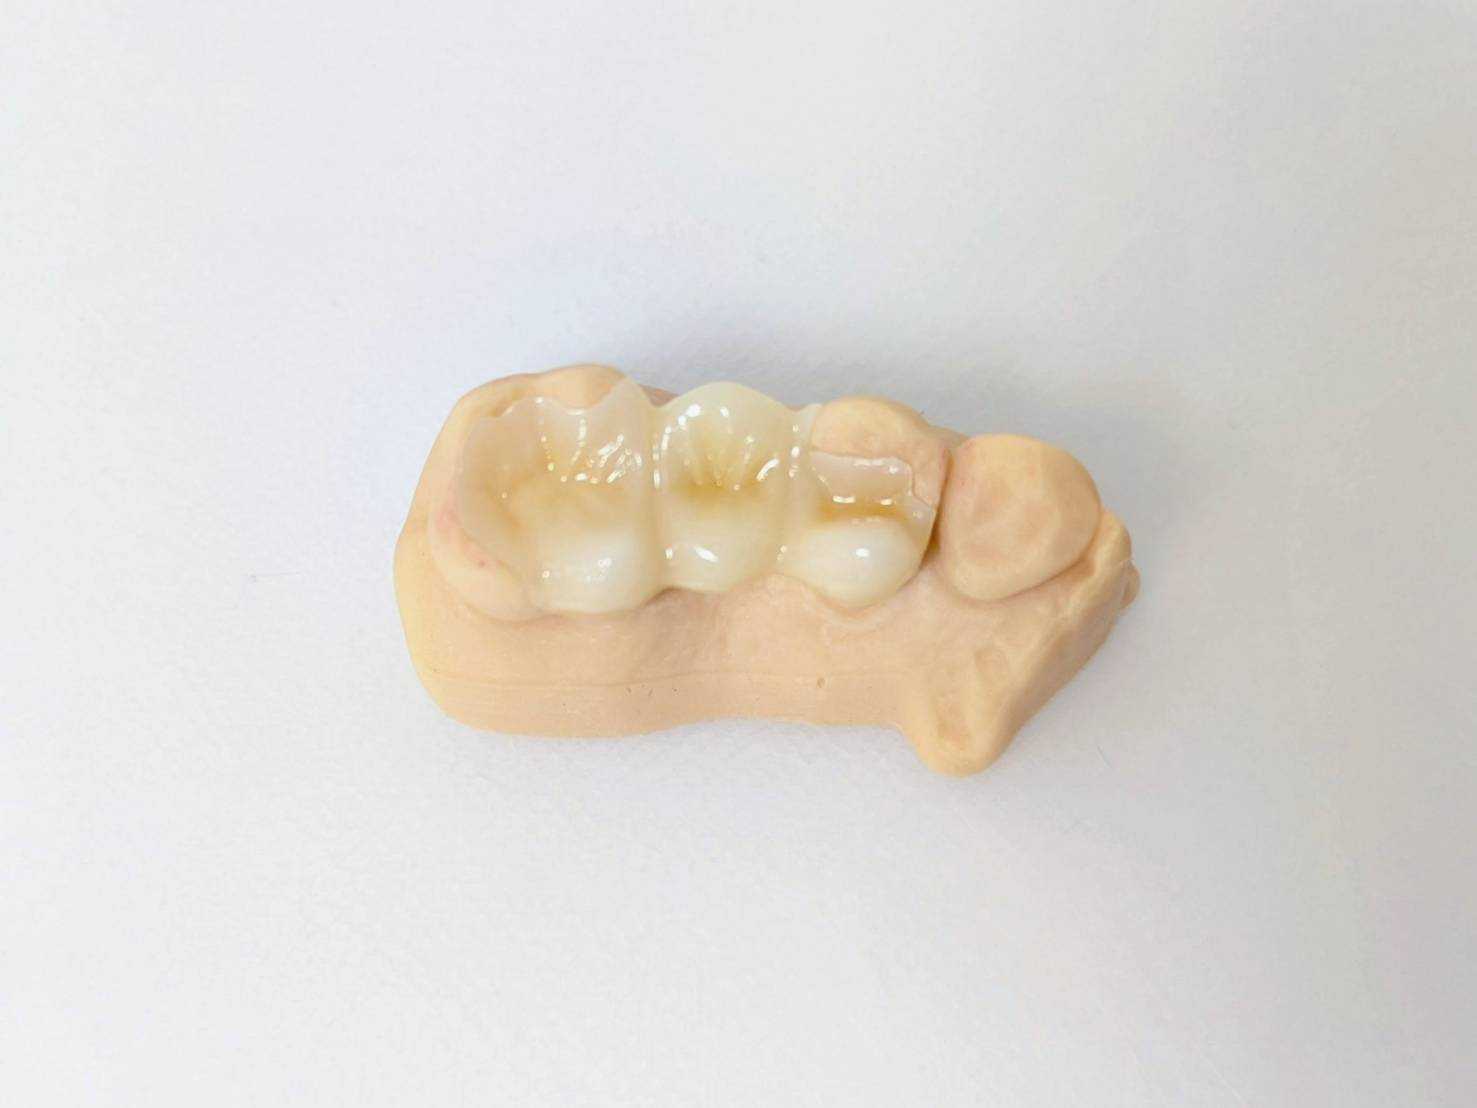

30代女性「銀歯を白くしたい」

施術名

e-max インレー

治療にかかった費用

44000円

治療にかかった期間

治療回数2回 約2週間から3週間

治療のリスク、副作用

強い力がかかると割れることがある

むし歯が深い場合術後にしみる症状が残ることがある